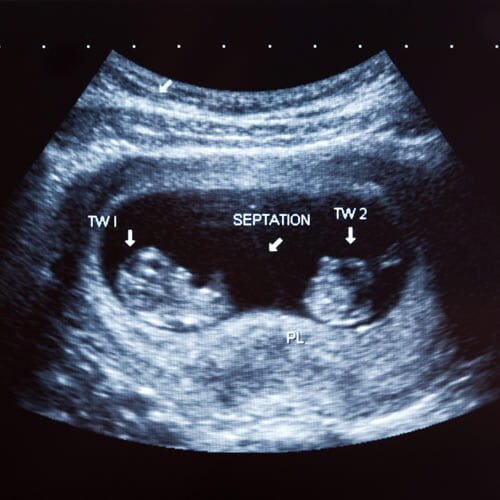

A melhor clínica de Ultrassom de Congonhas

Fundada por profissionais apaixonados pela profissão, nossa clínica atende toda a região.

Com atendimento extremamente especializado, a Ultrassom Congonhas garante um diagnóstico preciso, ético e com preço acessível. Contamos com uma equipe dedicada à boa prática médica e em constante aprimoramento científico.